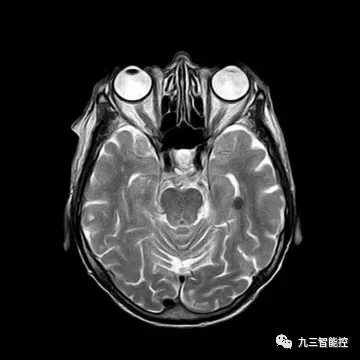

(5)大脑核磁共振图像(侧面)

(6)大脑核磁共振图像(正面)